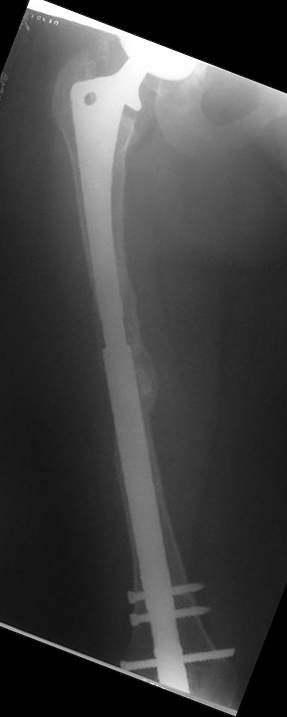

Female, rheumatoid, THA in 2003, car accident in 2006, failed plating. Nailing in Oct 2007. The nail is solid with hollow proximal part where the stem is docked. Last images are in 1 year after

nailing.

I heard from many european colleagues about anecdotal use of old hollow Kuntscher nails for that purpose. Prof. R.Schnettler (Germany) recently told about 57 cases. I have only 2 such cases done last year, both on cementless stem. This approach is very attractive by that we achieve the same goal - "new long stem" but much less invasive.

I have refreshed respect for the mighty femur and it’s incredible/remarkable ability to unite, regardless of what we do to it.

The femur responded by failure to Mennen plating (DePuy Bridge plate). So i would add that the ability to unite is realized in mechanically and biologically sound conditions.